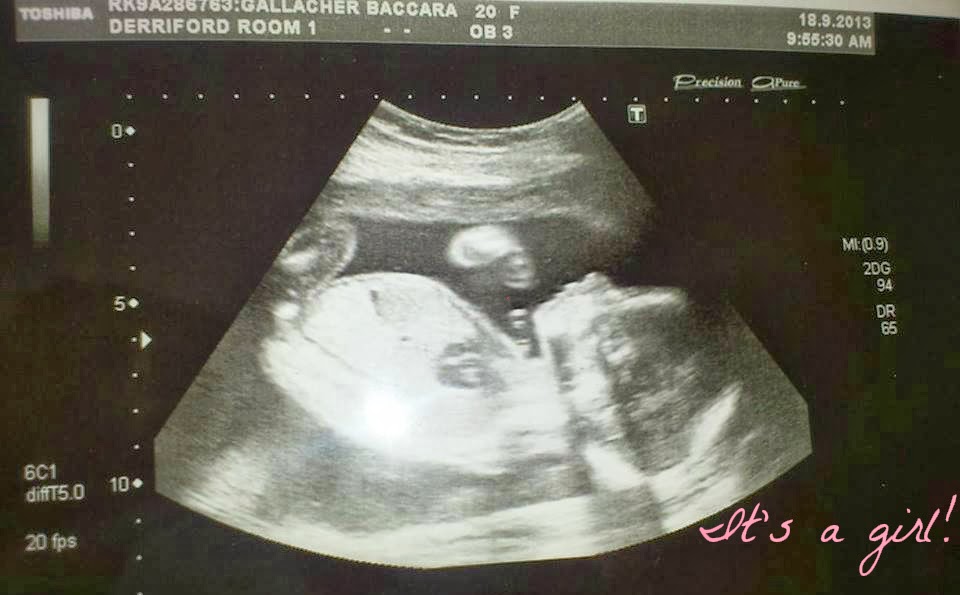

BUMP & SCAN PICS 6-20 WEEKS AND SCAN PHOTO!